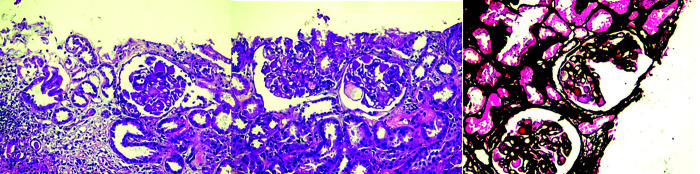

贝伐单抗和阿特唑单抗联合治疗是治疗晚期肝细胞癌(HCC)的首选组合之一,然而单药治疗的证据并不令人信服。我们报告了一个50多岁的男性HCC合并脊柱转移的病例,他对联合治疗有很好的反应。然而,他继发于贝伐单抗后出现了严重的蛋白尿和高血压,在18个周期后不得不停药。在做出明智的决定后,继续使用阿特唑单抗,患者表现出持续的反应。迄今为止,他在停用贝伐单抗后又接受了16个额外周期的atezolizumab单药治疗,并继续显示出持续的反应,目前无进展生存期超过30个月。如我们的报告所述,atezolizumab作为长期单药治疗的有效性是初始联合治疗的残余效应,还是HCC对单独免疫治疗具有内在反应,需要进行前瞻性评估。如何引用本文:Naviwala MSS, Shoaib D, Khan WA等。晚期肝细胞癌停止使用VEGF抑制剂后免疫治疗完全缓解:1例报告。中华肝病与胃肠病杂志;2009;14(2):246-250。

Bevacizumab and atezolizumab combination is one of the preferred combinations for managing advanced hepatocellular carcinoma (HCC), while the evidence on monotherapy with either agent is not convincing. We present a case of a man in his 50s diagnosed with HCC with spinal metastases who showed a good response to combination therapy. However, he developed severe proteinuria and hypertension secondary to bevacizumab, which had to be discontinued after 18 cycles. After an informed decision, atezolizumab was continued and the patient showed a sustained response. Till date, he has received 16 additional cycles of atezolizumab monotherapy after discontinuation of bevacizumab and continues to show a persistent response, with a progression-free survival of over 30 months now. It needs to be prospectively evaluated if atezolizumab's effectiveness as monotherapy for extended periods, as in our report, is a residual effect of initial combination therapy or if HCC is intrinsically responsive to immunotherapy alone.